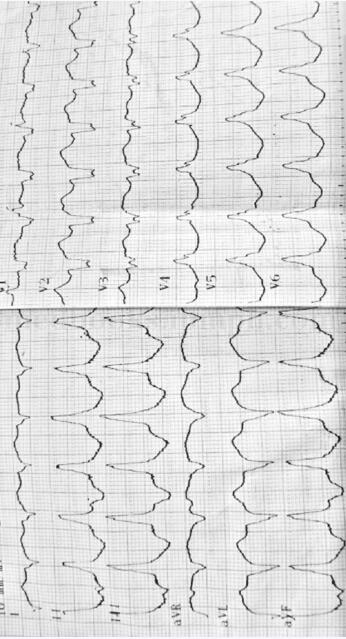

1.心电图检查

心房率:75次/分,心室率:127次/分,QRS波群形态畸形,P波与QRS波无关,QRS波频率>P波频率(图61-1)。

图61-1 患者入院时的心电图所见

思维提示:重要的检查结果为心电图检查。室性心动过速的心电图特征为:①3个或以上的室性期前收缩出现,②QRS波群形态畸形,时速超过0.12s,ST-T波方向与QRS波群主波方向相反,③心室率通常为100~250次/分;心律规则,也可略不规则,④心房独立活动与QRS波群无固定关系,形成房室分离;偶尔个别或所有心室激动逆传夺获心房,⑤通常发作突然开始,⑥心室夺获与室性融合波:室速发作时少数室上性冲动可下传心室,产生心室夺获,表现为在P波之后,提前发生一次正常的QRS波群,室性融合波的QRS波群形态介于窦性与异位心室搏动之间,其意义为部分心室夺获。心室夺获与室性融合波的存在对确立室性心动过速诊断提供重要依据。患者的心电图表现为心室率:127次/分,QRS波群形态畸形,P波与QRS波无关,可见心室夺获与室性融合波,由此可见心电图检查符合室性心动过速诊断,进一步地处理是对症支持治疗,营养心肌,纠正心律失常,必要时可行电复律治疗。